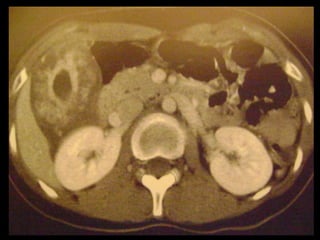

Colecistite aguda

Achados na TC: cálculos biliares, espessamento da

parede, alterações inflamatórias

perivesiculares, bile com alta

atenuação, borramento da interface VB-fígado e

aumento transitório da atenuação do fígado

perivesicular;